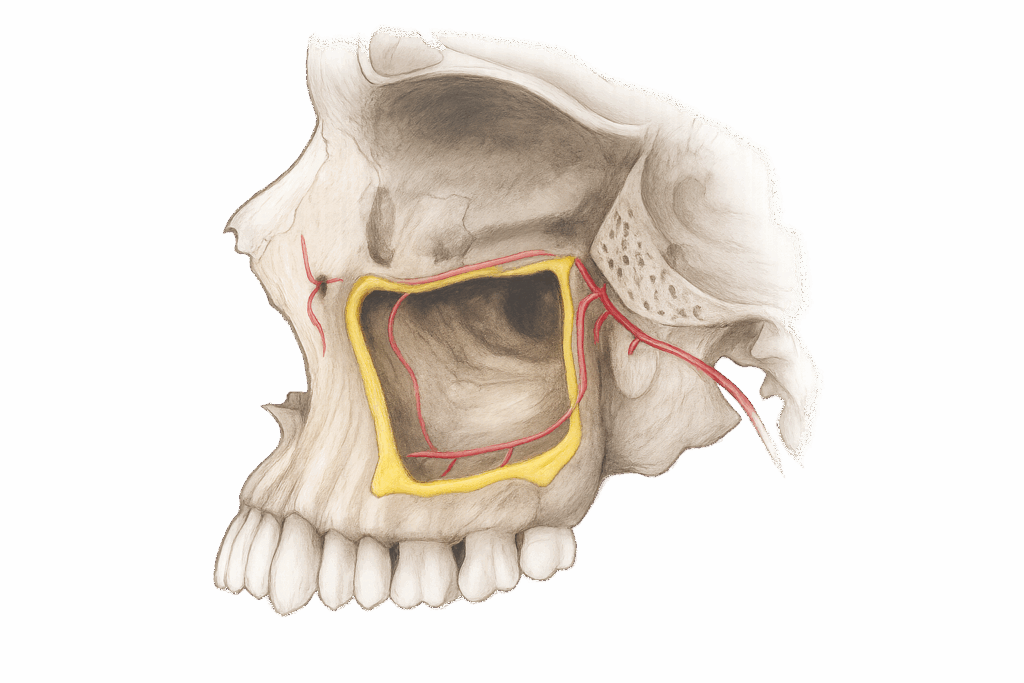

그 이유는 상악동의 존재입니다.

이에 민락 치과 에서 설명해 드리면

얼굴의 양쪽 광대 쪽에 존재하는

부비동의 일종으로써

우리가 숨을 쉬고 소리를 내는 데에

큰 역할을 하는 주요 조직입니다.

그러나 치조골의 두께가 얇아짐과 동시에

이곳이 아래쪽으로 내려오게 됩니다.

이를 상악동의 함기화라고 말하며

임플란트를 식립하는 데 있어

큰 위험 요소가 될 수 있습니다.

얇은 막으로 구성되어 있어

쉽게 찢어지고 천공으로 이어지는

부작용을 일으킬 수 있기 때문입니다.